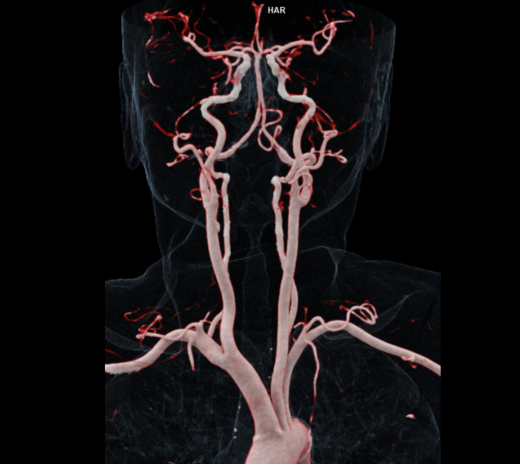

• 脑神经科:脑部微细血管显影更清晰,提升中风及复杂病变诊断的准确度。

脑部和颈部血管